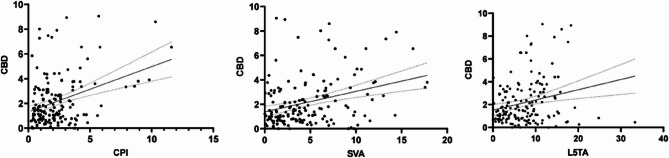

Further stepwise linear regression analysis indicated that L5TA (R²=0.204, p < 0.05), CPI (R²=0.128, p < 0.05), and SVA (R²=0.172, p < 0.05) substantially influenced CBD (scatter plot demonstrated in Fig. 4).